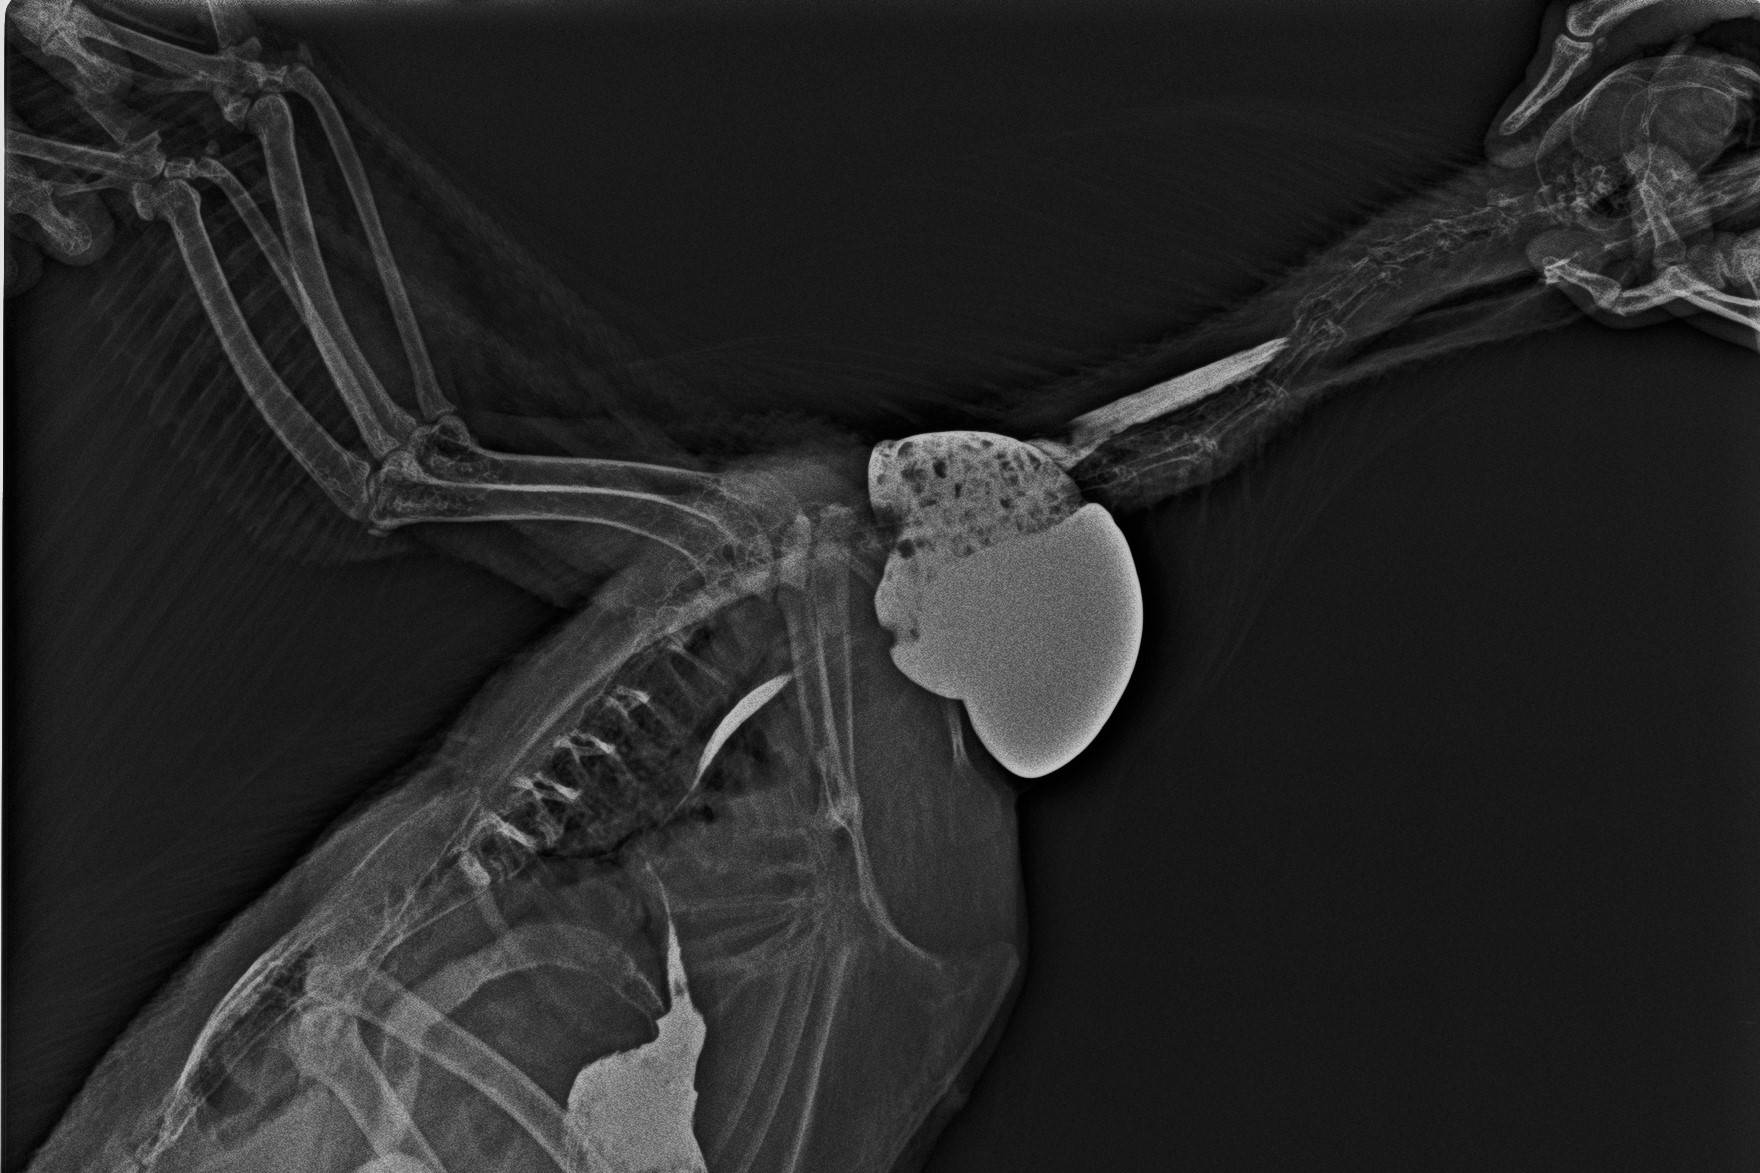

こちらはニワトリのレントゲン写真です。白く造影されているのが「そ嚢」です。